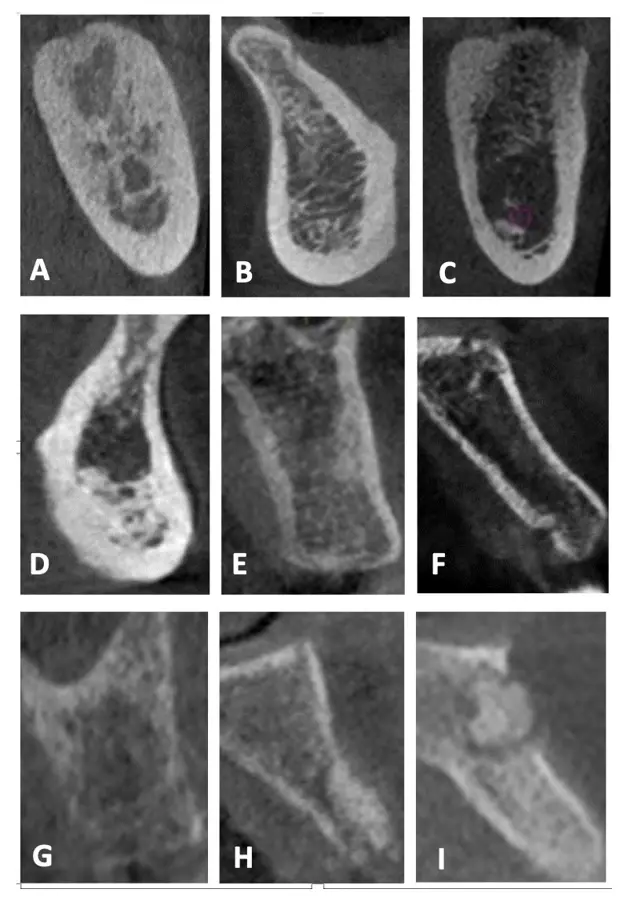

Las clasificaciones tradicionales asocian la calidad ósea con ciertos sectores en los maxilares

Por ejemplo, se dice que el sector anteroinferior de la mandíbula suele presentarse hueso tipo I y en el posteroinferior tipo II. La variante en la zona posterioinferior mandibular se debe a que, a pesar de tener una buena cortical ósea y cantidad de hueso esponjoso, la dimensión de los espacios medulares es muy amplia y el grosor de las trabéculas tan finas como el espesor de un cabello11 (Figura 3).